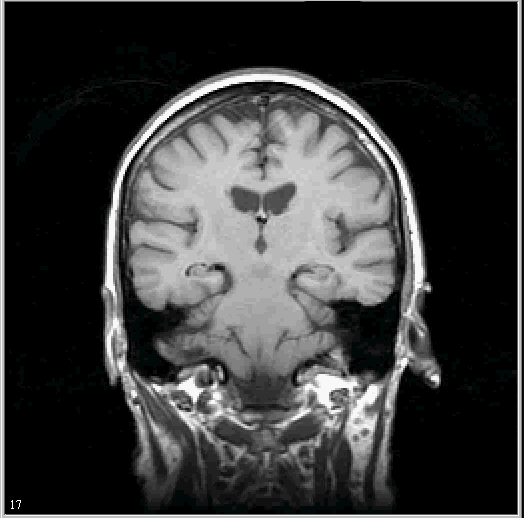

MIPAV provides tools that allow researchers to automatically, semi-automatically, and manually identify and modify volumes of interest (VOIs). Nodes on the VOI can be moved or deleted, and new points can be added. VOI types include point, 2D line, 2D rectangle, 3D rectangle, 2D ellipse, 2D polygon, 3D polygon, and interactive level-set.